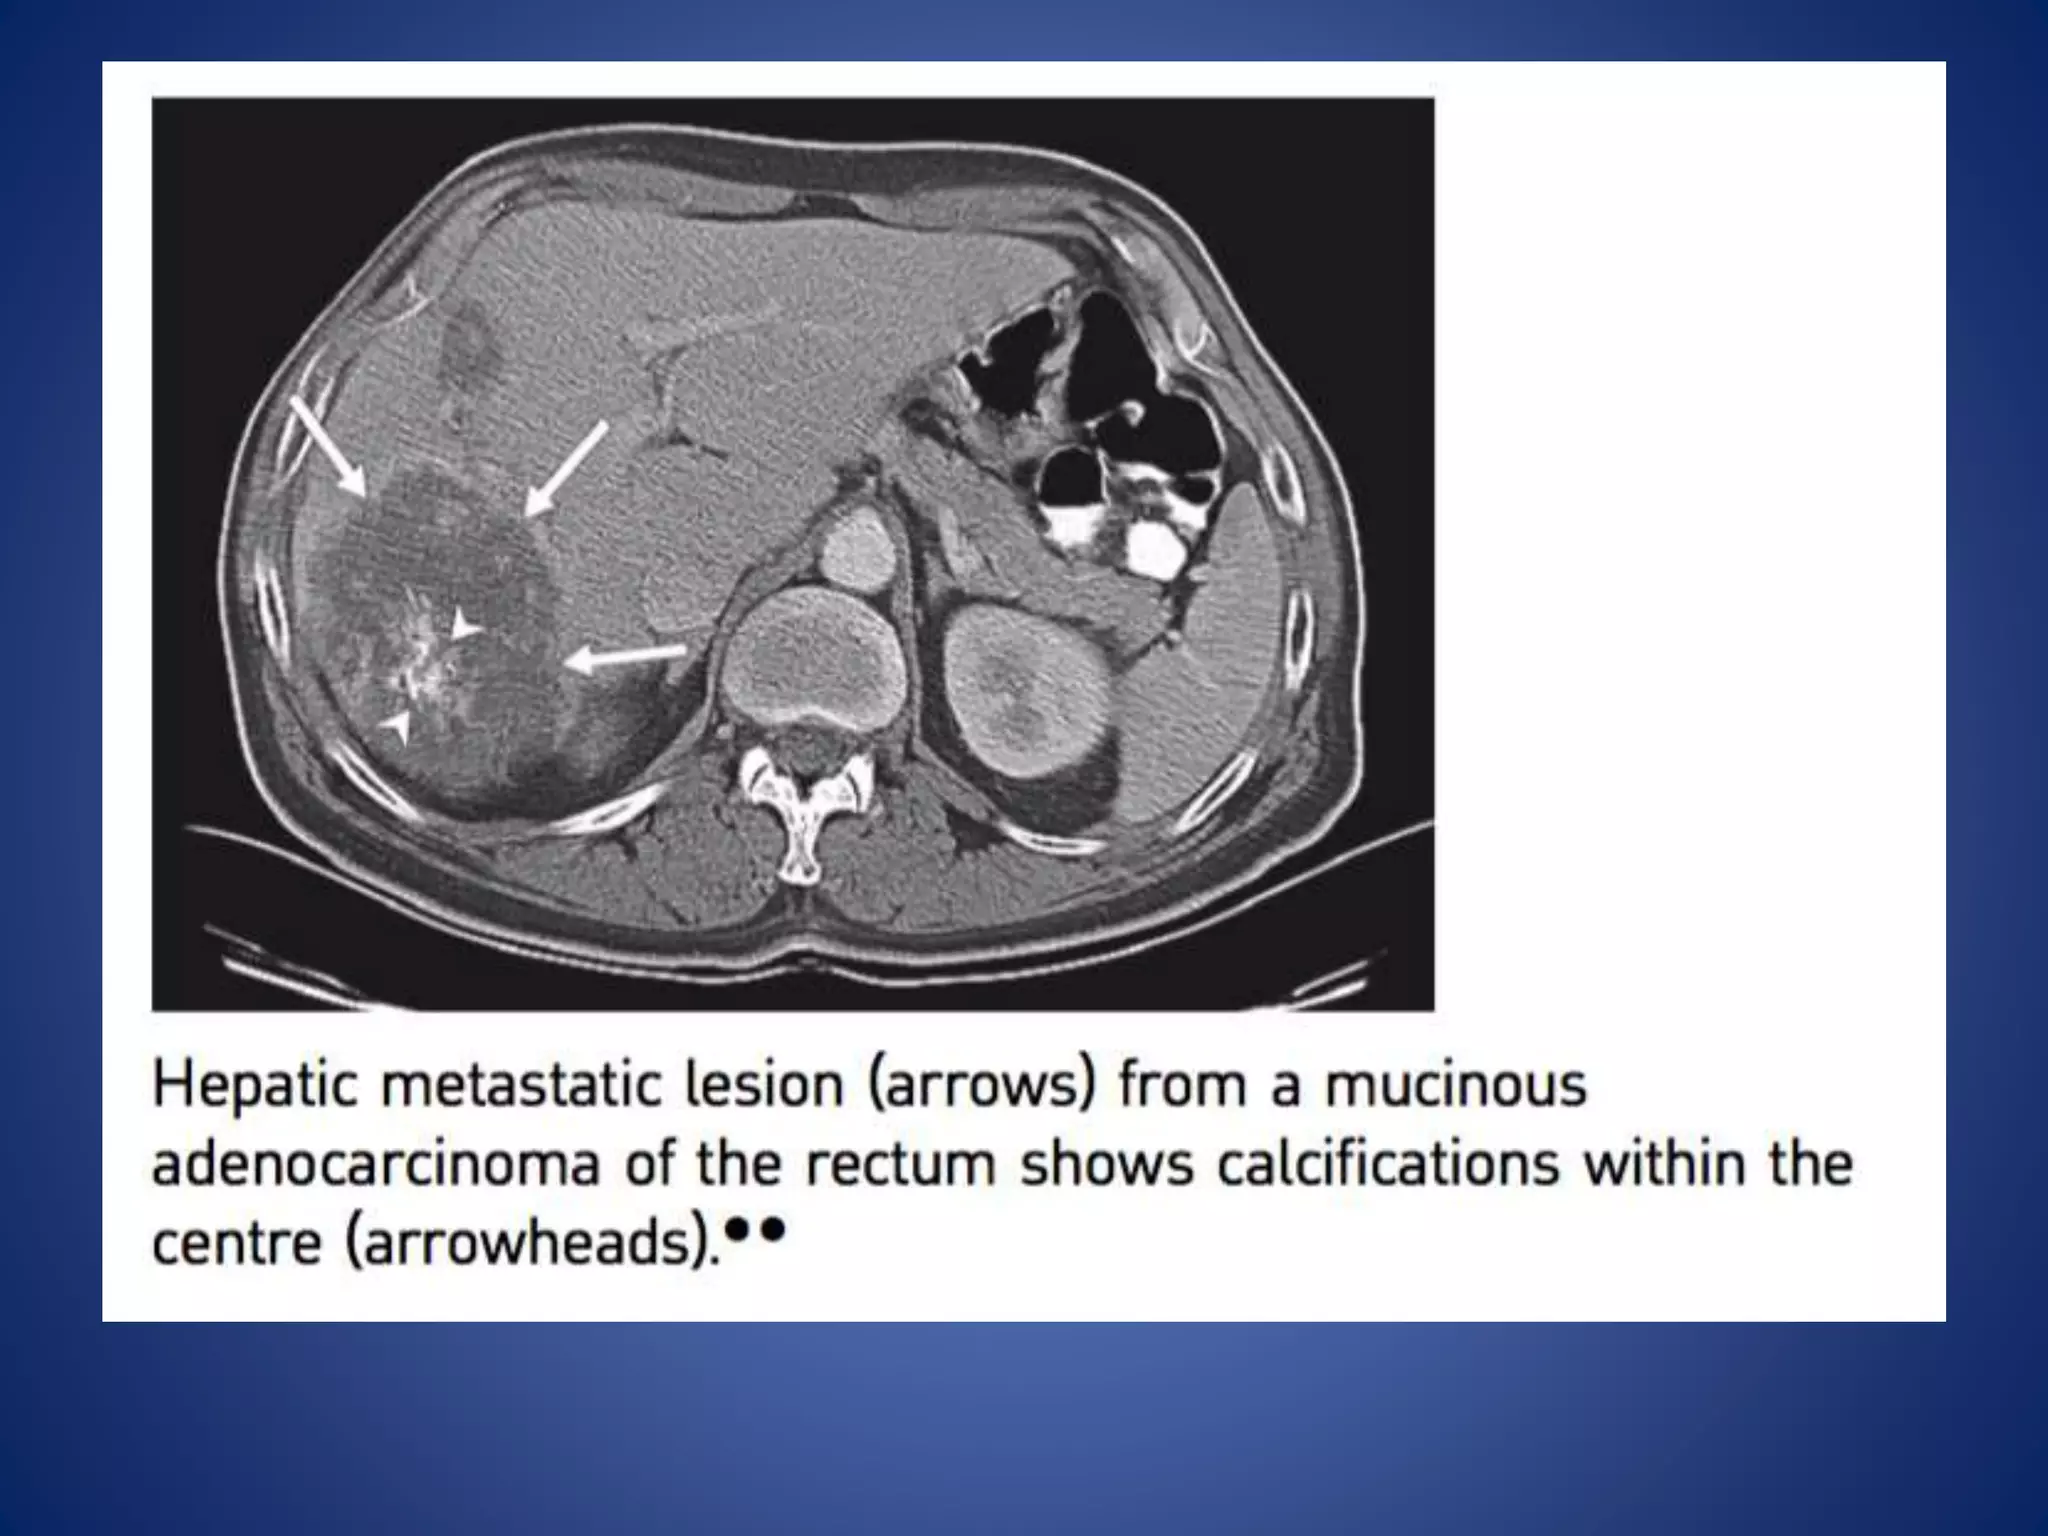

This document discusses various malignant liver lesions including hepatocellular carcinoma (HCC), liver metastases, and angiosarcoma. HCC is the most common primary liver cancer, often occurring in cirrhotic livers, and can appear solitary or multifocal on imaging. Liver metastases commonly spread from gastrointestinal or non-gastrointestinal primary cancers via the hepatic artery or portal vein. Angiosarcoma is a rare malignant vascular liver tumor associated with toxins like polyvinylchloride and arsenic.